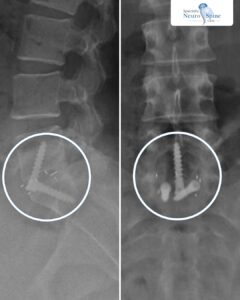

In 2022, Dr. Firas Husban became the first surgeon in the Middle East and North Africa (MENA) region to perform Oblique Lumbar Interbody Fusion (OLIF) surgery. Previously, OLIF – a groundbreaking minimally invasive spine procedure – was only accessible to patients overseas.

Unlike traditional open spine surgery, OLIF offers patients smaller incisions, reduced blood loss, shorter recovery times, and lower complication risks. Dr. Husban has since performed dozens of successful OLIF procedures with outstanding results — treating patients from adolescents to those in their 80s.

From Mohammad Al-Shammari, an 81-year-old patient from Saudi Arabia who regained mobility, to Dalia, a 26-year-old from Iraq who returned to full activity, and Zainab, whose procedure has remained successful for over a decade—Dr. Husban’s cases demonstrate that OLIF delivers lasting outcomes for patients of all backgrounds.